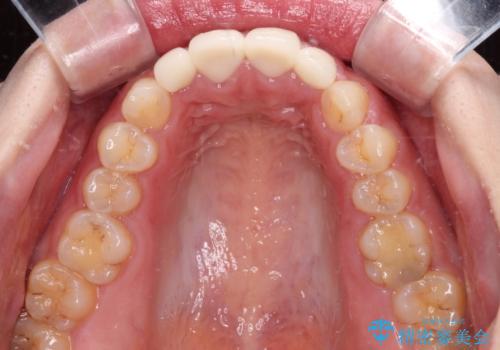

- 前歯の矮小歯と捻れや変色を気にして来院された患者様です。

結婚式が近いということもあり、前歯4本をオールセラミッククラウンにて補綴治療することとしました。

前歯の捻れは、オールセラミッククラウンよりも矯正治療による改善の方が、歯を削らなくて済むためお勧めとなります。

しかし、矮小歯の改善はオールセラミッククラウンでの補綴治療が必要であり、幅径のバランスを取る必要があるため、4前歯の補綴治療を選択しました。